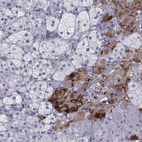

Immunohistochemistry analysis in human adrenal gland and liver tissues using HPA073224 antibody. Corresponding SLC18A2 RNA-seq data are presented for the same tissues.